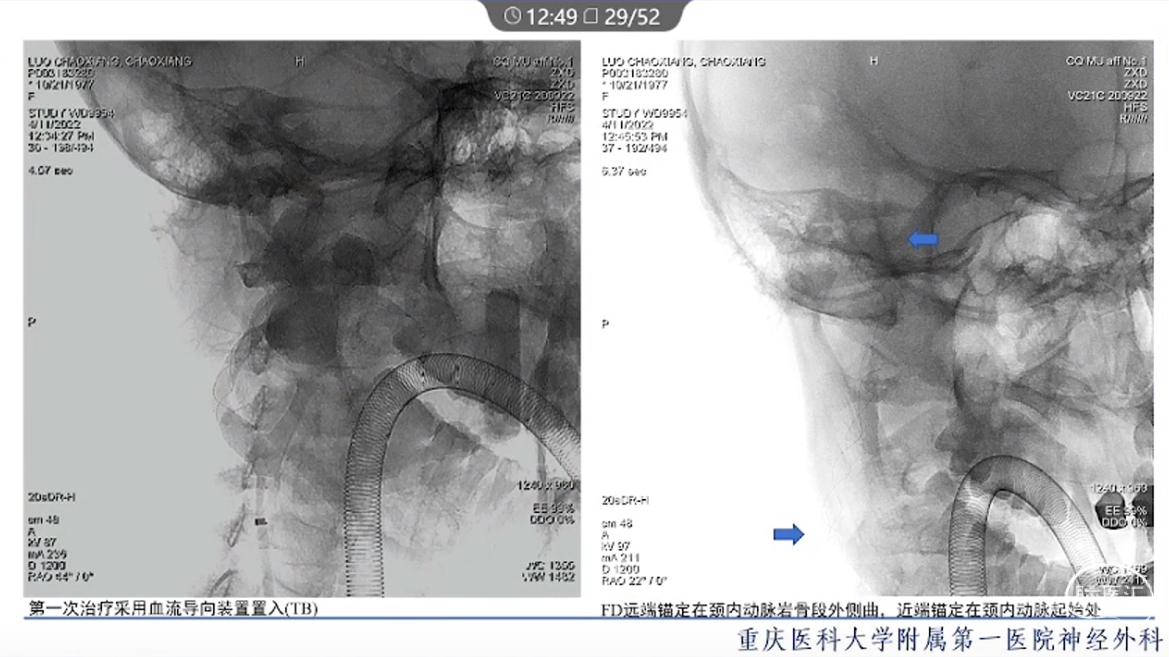

·颈内动脉颈段动脉瘤治疗方式有血管内治疗、外科手术和保守治疗。

·血管内治疗是最常见的治疗方式,随着血管内介入技术的发展和材料的进步,越来越多的动脉瘤可以通过血管内途径治疗。

·对于血管扭曲、血管直径大以及存在抗血小板禁忌的动脉瘤患者,特别是对于颈段大型或巨大型动脉瘤的治疗,常需要外科手术治疗。